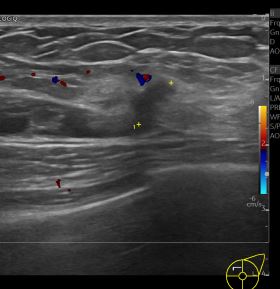

상기환자 외부검사이상으로 정밀검사위해 내원하신 40대 여성분으로

좌측유방 혹 총조직검사 시행해 유방암 진단되었습니다.